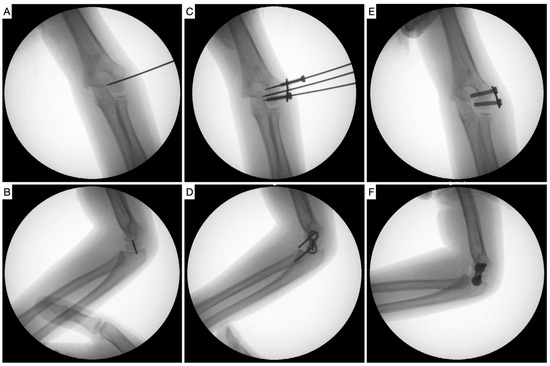

- Verka, P.S. A novel minimally invasive method in pediatric cubitus varus deformity, distal lateral humerus hemiepiphysiodesis: A case report. J. Pediatr. Neurol. Disord. 2021, 4, 1–2. [Google Scholar]

- Soldado, F.; Diaz-Gallardo, P.; Cherqaoui, A.; Nguyen, T.-Q.; Romero-Larrauri, P.; Knorr, J. Unsuccessful mid-term results for distal humeral hemiepiphysiodesis to treat cubitus varus deformity in young children. J. Pediatr. Orthop. B 2022, 31, 431–433. [Google Scholar] [CrossRef]

- Métaizeau, J.-P.; Wong-Chung, J.; Bertrand, H.; Pasquier, P. Percutaneous Epiphysiodesis Using Transphyseal Screws (PETS). J. Pediatr. Orthop. 1998, 18, 363–369. [Google Scholar] [CrossRef]